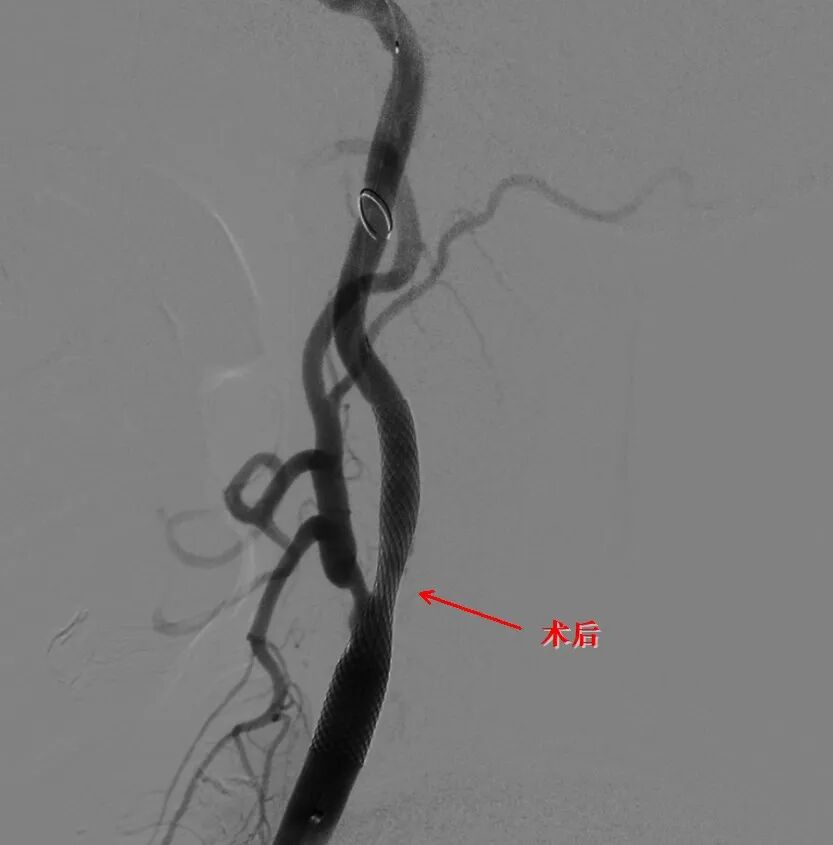

• 神经外科接力攻坚:邱耀忠主任医师、李建副主任医师携手,针对同侧的两个动脉瘤植入血流导向密网支架,隔绝血流冲击,预防破裂。

术后影像显示:脑动脉血流畅通,动脉瘤处理稳定,无出血或缺血并发症。